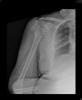

Fractura impactada de húmero .